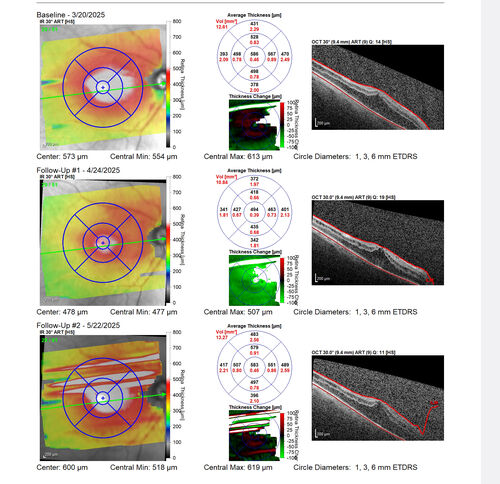

Paclitaxel induced cystoid macular edema - reversed when chemo stopped

74 year old retired physician  About 2-3 weeks ago there was gradual vision loss in the right eye. The patient was seen by an ophthalmologist who saw macular swelling and injected vabysmo. He has been on chemotherapy (Carbiplatin and Carboxytaxol for 2 cancers - advanced prostrate diagnosed 2019 - has had brain surgery AND squamous lung cancers treated with radiation)